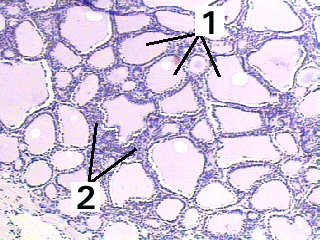

| Thyroid gland | Slide 55 (H & E) |

A magnification of the thyroid demonstrating the arrangement of the glandular cells into follicles.

Fig 55-002 Wheater 3rd Ed p.309-311 or 4th Ed p.96 |